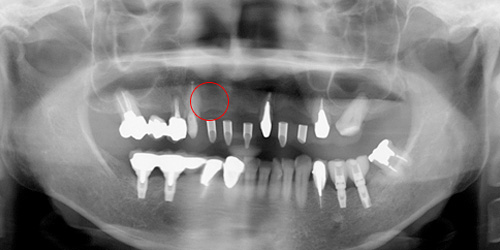

Before

赤丸の部位にインプラントを埋入する予定です。